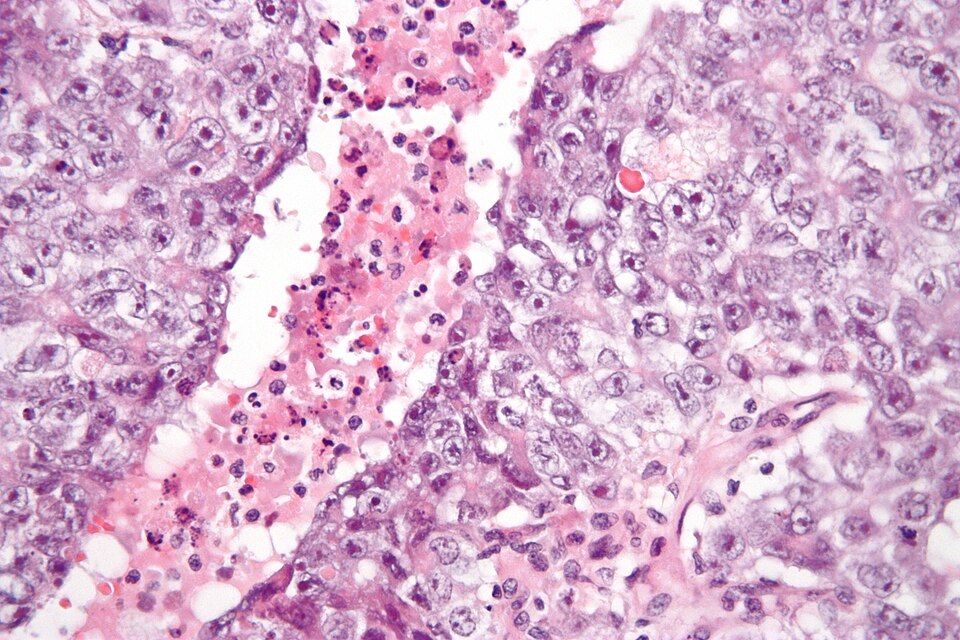

English: High magnification micrograph of an embryonal carcinoma, a type of germ cell tumour. H&E stain.

Features:

• Cell borders indistinct.

• Mitoses common.

• Variable architecture:

• Tubulopapillary,

• Glandular,

• Solid,

• Embryoid bodies - ball of cells in surrounded by empty space on three sides.

• Nuclei overlap.

• +/- Necrosis.